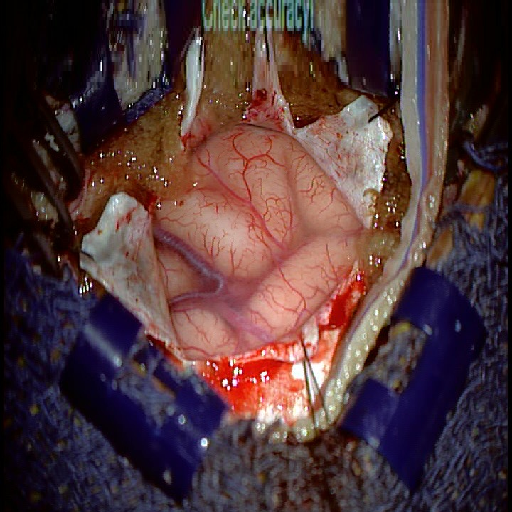

We tested our method retrospectively on 6 clinical datasets from 6 patients (cases) (see Fig. 5). These consisted of preoperative T1 contrast MRI scans and intraoperative images of the brain surface after dura opening. Cortical vessels around the tumors were segmented and triangulated to generate 3D meshes using 3D Slicer. We generated 100 poses for each 3D mesh (i.e.: each case) and used a total of 15 unique textures from human brain surfaces (different from our 6 clinical datasets) for synthesis using . In order to account for potential intraoperative brain deformations [4] we augment the textured projection with elastic deformation [21] resulting in approximately 1500 images per case. The surgical images of the brain (left image of the stereoscopic camera) were acquired with a Carl Zeiss surgical microscope. The ground-truth poses were obtained by manually aligning the 3D meshes on their corresponding images.

Fig. 5 shows our results as Augmented Reality views with bounding boxes and overlaid meshes. Our method produced visually consistent alignments for all 6 clinical cases without the need for initial registration. Because our current method does not account for brain-shift deformation, our method produced some misalignment errors. However, in all cases, our predictions are similar to the ground truth.